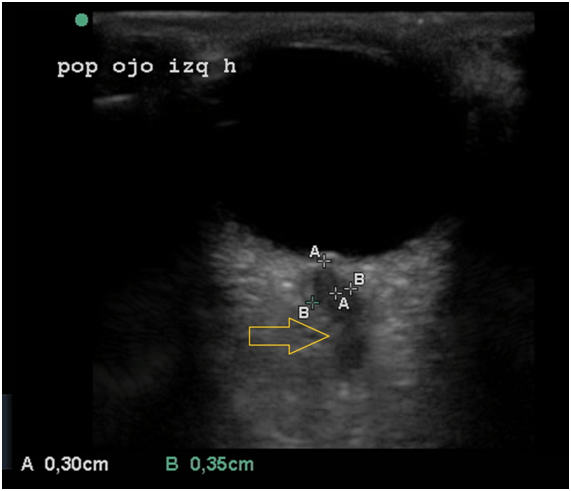

Fifteen minutes after the surgical closing of the eyelid we repeated the assessment of the ONSD and we tried to see the location of the cut in the Optic Nerve Sheath for the eye chosen by the surgeons (Figure 1 & 2). The new measurements were: RE: 70-70 mm and for the LE (the eye chosen for the fenestration): 54-35 mm.  The global mean after the surgery was 57,25mm. A decrease in the sheath around the ON could demonstrate the place where the cut was made at the Nerve Sheath (Figure 2).

Figure 2 US IMAGE of the Left Eye Post Surgery: ONSD 35mm. Yellow Arrow: Site of the fenestration.